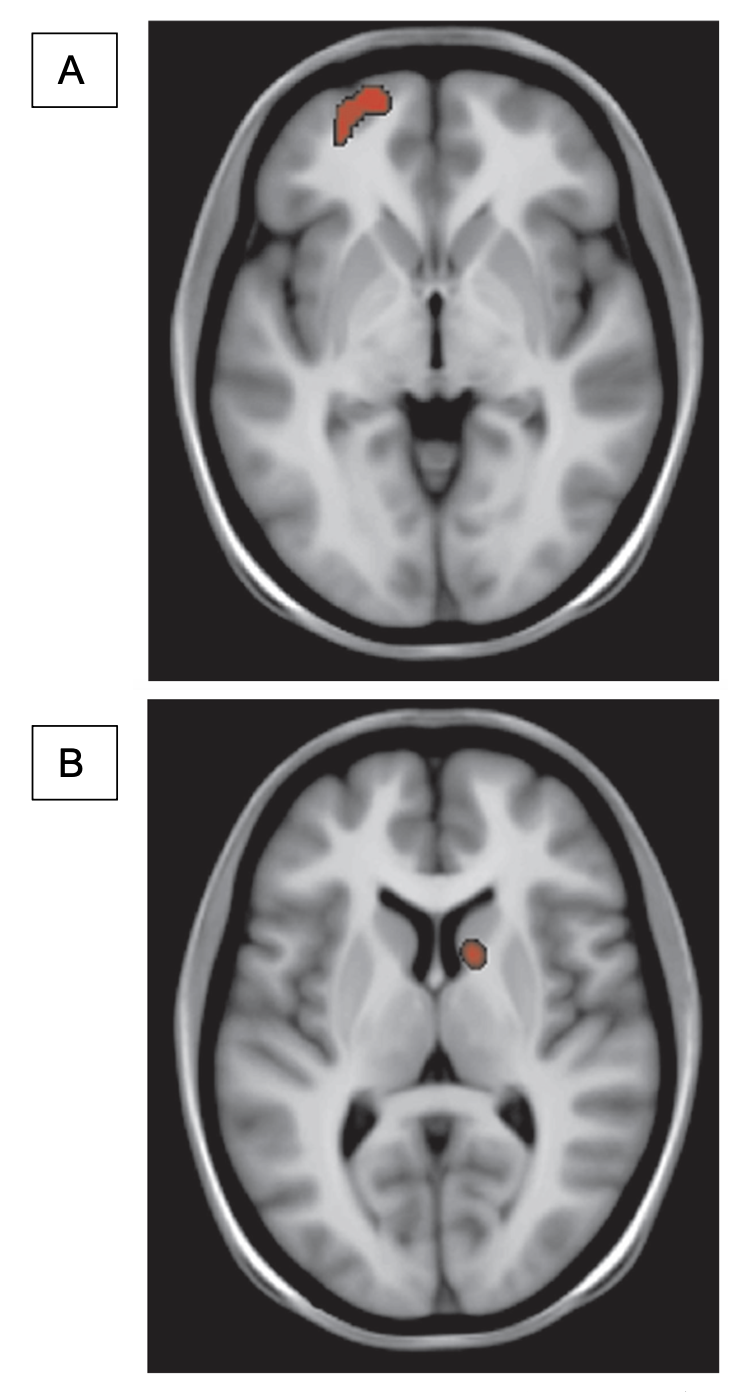

Using PET scan and MRI, Lundby et al., (2011) inferred that the afferent projections of colorectum are the target of SNM in FI patients. They measured local increase of regional cerebral blood flow (rCBF) caused by increased neural activity through analyzing changes in the uptake of a radiolabeled tracer of blood flow. The initial stimulation of sacral nerves through an implant activated a region on the contralateral frontal cortex but after chronic stimulation this activation was shifted to ipsilateral caudate nucleus which is a region of the brain involved in learning and reward processing (Fig.2). A similar cerebral effect has also been observed in vagus nerve stimulation (18).

Figure 2: Changes in regional cerebral blood flow

Figure 2. Changes in regional cerebral blood flow (rCBF) tested via PET/MRI co-registration. (A) The red region shows initial activation of the contralateral frontal cortex 30 minutes after onset of sacral nerve stimulation. (B) Red shows activation of the ipsilateral caudate nucleus after 2 weeks of sacral nerve stimulation. Statistical significance was at P < 0.05. [Figures from Lundby et al.,18].